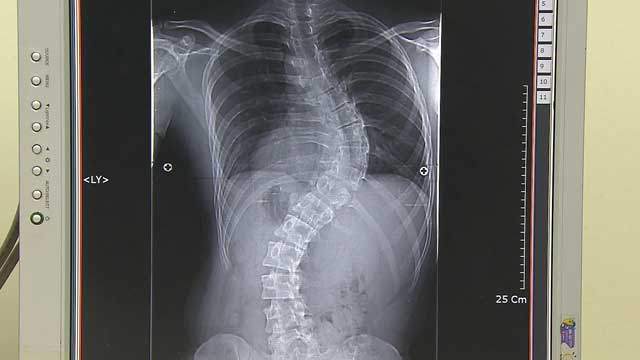

[박광식의 건강365] 가방 한쪽만 멘다고 '척추측만증'?! 80%가 원인 몰라

▷박광식: 척추가 C자나 S자로 휘는 척추측만증이 있으면 모두 치료를 받아야 하는 건가요?

▶서승우: 각도가 20도 미만일 때는 운동, 스트레칭 정도 하면서 관리를 하고요. 적극적인 치료개념보다는 더 휘지 않도록 바른 자세하고 스트레칭해주는 예방적 개념으로 생각하면 됩니다. 20도 이상 되면 계속 휘어질 가능성이 조금 있거든요. 그러다 보니까 20도 이상이면 보조기를 채우고요. 40도 이상이면 성인이 돼서도 계속 조금씩 휠 수 있기 때문에 한 40~50도 넘어가면 수술도 고려하게 됩니다.

▶서승우: 그렇지 않습니다. 척추측만증의 80%가 원인을 모르는 특발성 척추측만증입니다. 여성이 특히 많은데요. 관절이 휘는 질환들이 보통 여성이 많습니다. 엄지발가락이 휘는 종무지외반증이라는 것도 보통 하이힐 신어서 휜다고 많이 생각하시는데 꼭 하이힐이 원인은 아니고요. 여성에게 많이 있고 또 다리 휘는 것도 할머니들 보면 오자형 다리가 많이 있습니다. 그리고 신생아에서 고관절 빠지는 것도 보면 여아가 훨씬 더 많습니다.

▷박광식: 지금까지 건강 365 포인트 쏙쏙이었습니다. 척추측만증 치료와 수술을 결정하는 데 있어서 굽은 정도와 함께 성장상태를 고려해야 한다는 거 기억해 두면 좋겠습니다.